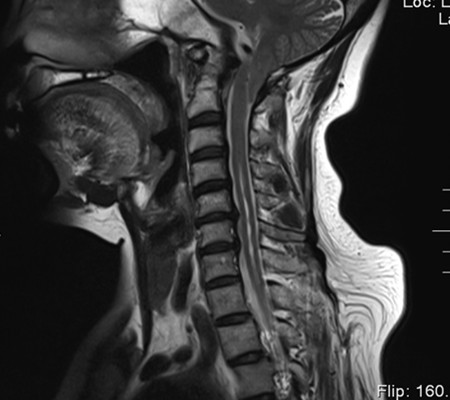

患者,女,53岁,以“颈肩部麻木、疼痛10月”入住神经外科一病区。该患者小脑扁桃体下疝畸形,颈椎先天发育也有异常。

主任刘增强、责任总医师巨涛等人就此病例进行了多次讨论。术前第一次运用先进的3D打印技术重塑了患者的寰枕部骨质及血管,证实了患者先天性寰椎后弓缺如。经过充分的术前准备,显微镜下切除了下疝的小脑扁桃体,结合3D打印结果,历时4小时完成了我院第一例后路减压+枕颈内固定术。患者术后3天下床活动,10天出院。

寰枕畸形是指枕骨底部及第一、二颈椎先天发育异常,除以骨骼为主的发育异常外,还合并有神经系统和软组织发育异常,包括扁平颅底、颅底陷入、寰枕融合、颈椎分节不全、寰枢椎脱位、小脑扁桃体下疝畸形等。